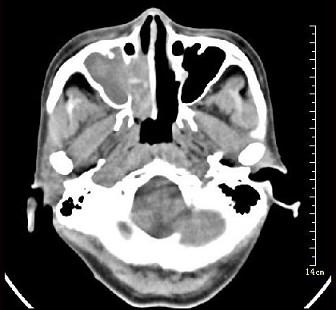

问题 女性,53岁,右侧鼻腔流血近1年,近来头痛,行CT检查如图所示,请选择正确的答案()

选项 A.鼻腔癌 B.鼻腔内息肉 C.副鼻窦炎 D.鼻腔炎性假瘤 E.鼻腔内血管瘤

答案 A